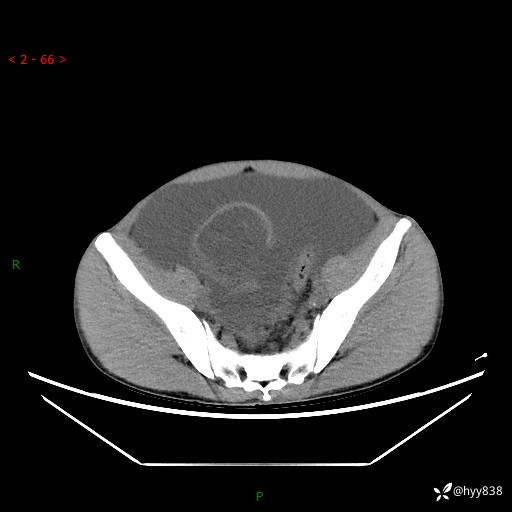

现病史:患者10天前无明显诱因出现腹部胀痛不适,无畏寒发热,无胸痛胸闷,无心慌气短,无恶心呕吐,无腹泻及黑便,无粘液血便及里急后重等症状,4天前在当地县人民医院就诊,行腹部CT示:下腹部占位性病变,腹腔及盆腔积液;今患者为求进一步诊治来我院治疗,门诊以“腹水”收治入院。 发病以来,精神饮食可,大小便正常,体重体力无明显变化。

腹部CT平扫+增强